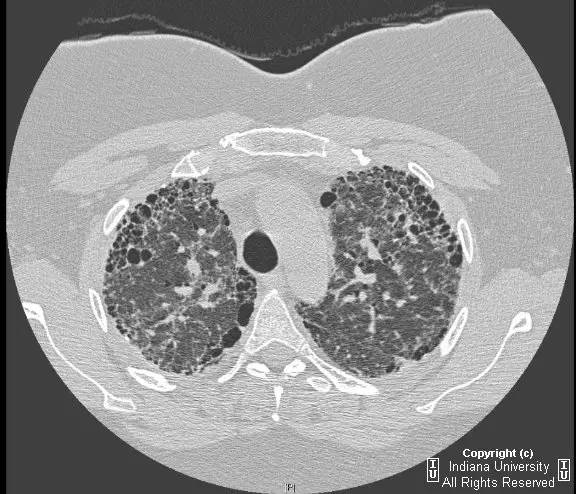

【影像学表现】胸片示双肺纹理增多,间质性透光度减低。无局灶性病变,气胸或胸腔积液。心脏及纵膈轮廓正常。CT示双肺弥漫间质性病变,累及所有肺叶,以下叶为著。肺间质增厚,结构扭曲,牵拉性支气管扩张,外周呈蜂窝状改变。肺动脉增粗,符合肺动脉高压。